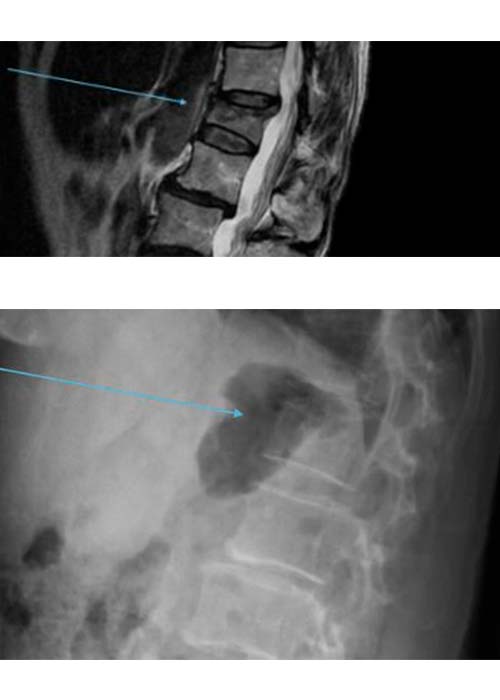

Una vez realizadas las pruebas de imagen, estas muestran una fractura acuñamiento de la 1º vértebra lumbar L1 sin que se vea afectado el muro posterior y con signos de edema agudo. Se decide realizar una cifoplastia.

Postoperatorio

Con esta técnica la recuperación es prácticamente inmediata.

El dolor desaparece inmediatamente.